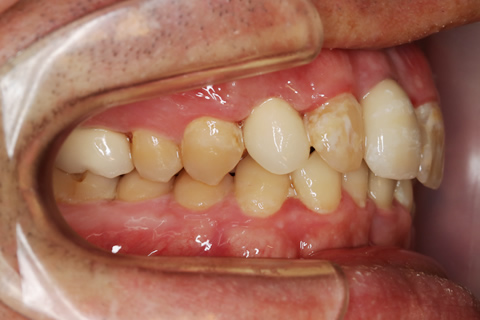

症例1

- 年齢・性別

- 55歳女性

- 治療期間

- 2ヶ月

- 抜歯

- なし

- 治療費

- 66万円

- 備考

- 右下6.7欠損

- 治療内容

- 右下6.7欠損部にインプラント埋入

- 施術の副作用(リスク)

- オペによる知覚障害。インプラントによる歯肉炎。インプラント脱落。